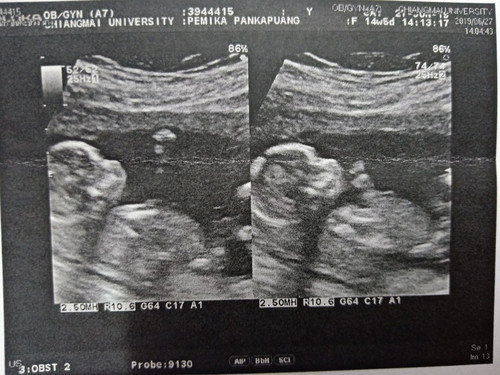

ครั้งแรกที่เห็นลูก 15w

มาโชว์เจ้าตัวเล็กกันหน่อยค่ะ ...วันนี้คัดกรองดาวน์จึงได้เห็นกันครั้งแรก ตื่นเต้นดีใจที่สุด เห็นเค้าดิ้นครั้งแรก ? 15w